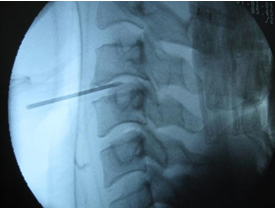

- Kỹ thuật mổ: bệnh nhân nằm ngửa, rạch da theo nếp cổ trên hay dưới bên phải tuỳ thuộc vào vị trí đĩa đệm cần can thiệp. Rạch các cân cổ rồi tách cơ, dùng farabeuf đưa khí-phế quản sang bên trái và bó mạch cảnh sang bên phải vào mặt trước cột sống. Cắm một kim đánh dấu vào khe liên đốt rồi chụp C-arm cột sống cổ nghiêng xác định vị trí kim từ đó tìm đến khe liên đốt có đĩa đệm cần can thiệp. Cắt dây chằng dọc trước, sau đó lấy đĩa đệm bằng curette và kerrison, khi đó có thể sử dụng một pince tự động để nâng và cố định vị trí của hai thân đốt sống tránh cho các chèn ép vào phía sau.

- Sau khi lấy bỏ sạch đĩa đệm, dây chằng dọc trước, gai xương, tiến hành đặt đĩa đệm cổ bằng dụng cụ chuyên dụng.

Hình 2. 1. Các đường rạch da theo vị trí thoát vị - Xác định tầng thoát vị bằng C-arm